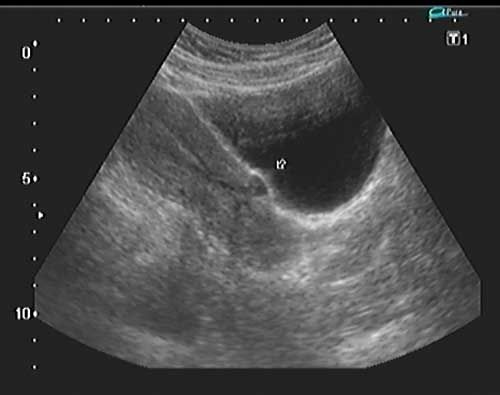

QUIZ: These images are from a young woman with pelvic pain. What do you see?